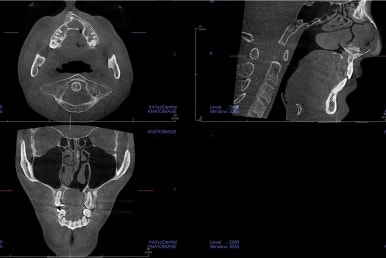

3. 초진 시 X-ray 분석

기본적인 파노라마 사진으로 치아 갯수, 뿌리 상태 등을 파악하고 CT 영상을 통해 골결손 부위, 비강 및 기도의 형태까지 파악해 줍니다.

특히 결손 부위 파악이 중요한 이유는 다음과 같습니다.

치아 이동 계획에서 결손 부위로는 치아를 움직이지 말아야 하며

해당 부위로의 이동이 생기면 잇몸/뼈의 결손 및 관리가 안될 수 있습니다.

입천장의 결손 부위가 악궁확장 시, 코와 입천장이 뚫려버리는 일도 생길 수 있습니다.

결손 부위의 결손 치아를 추후에 보철로 갯수를 추가할 때, 임플란트는 안되고 뼈의 안정성이 떨어지므로 특별한 주의가 필요합니다.